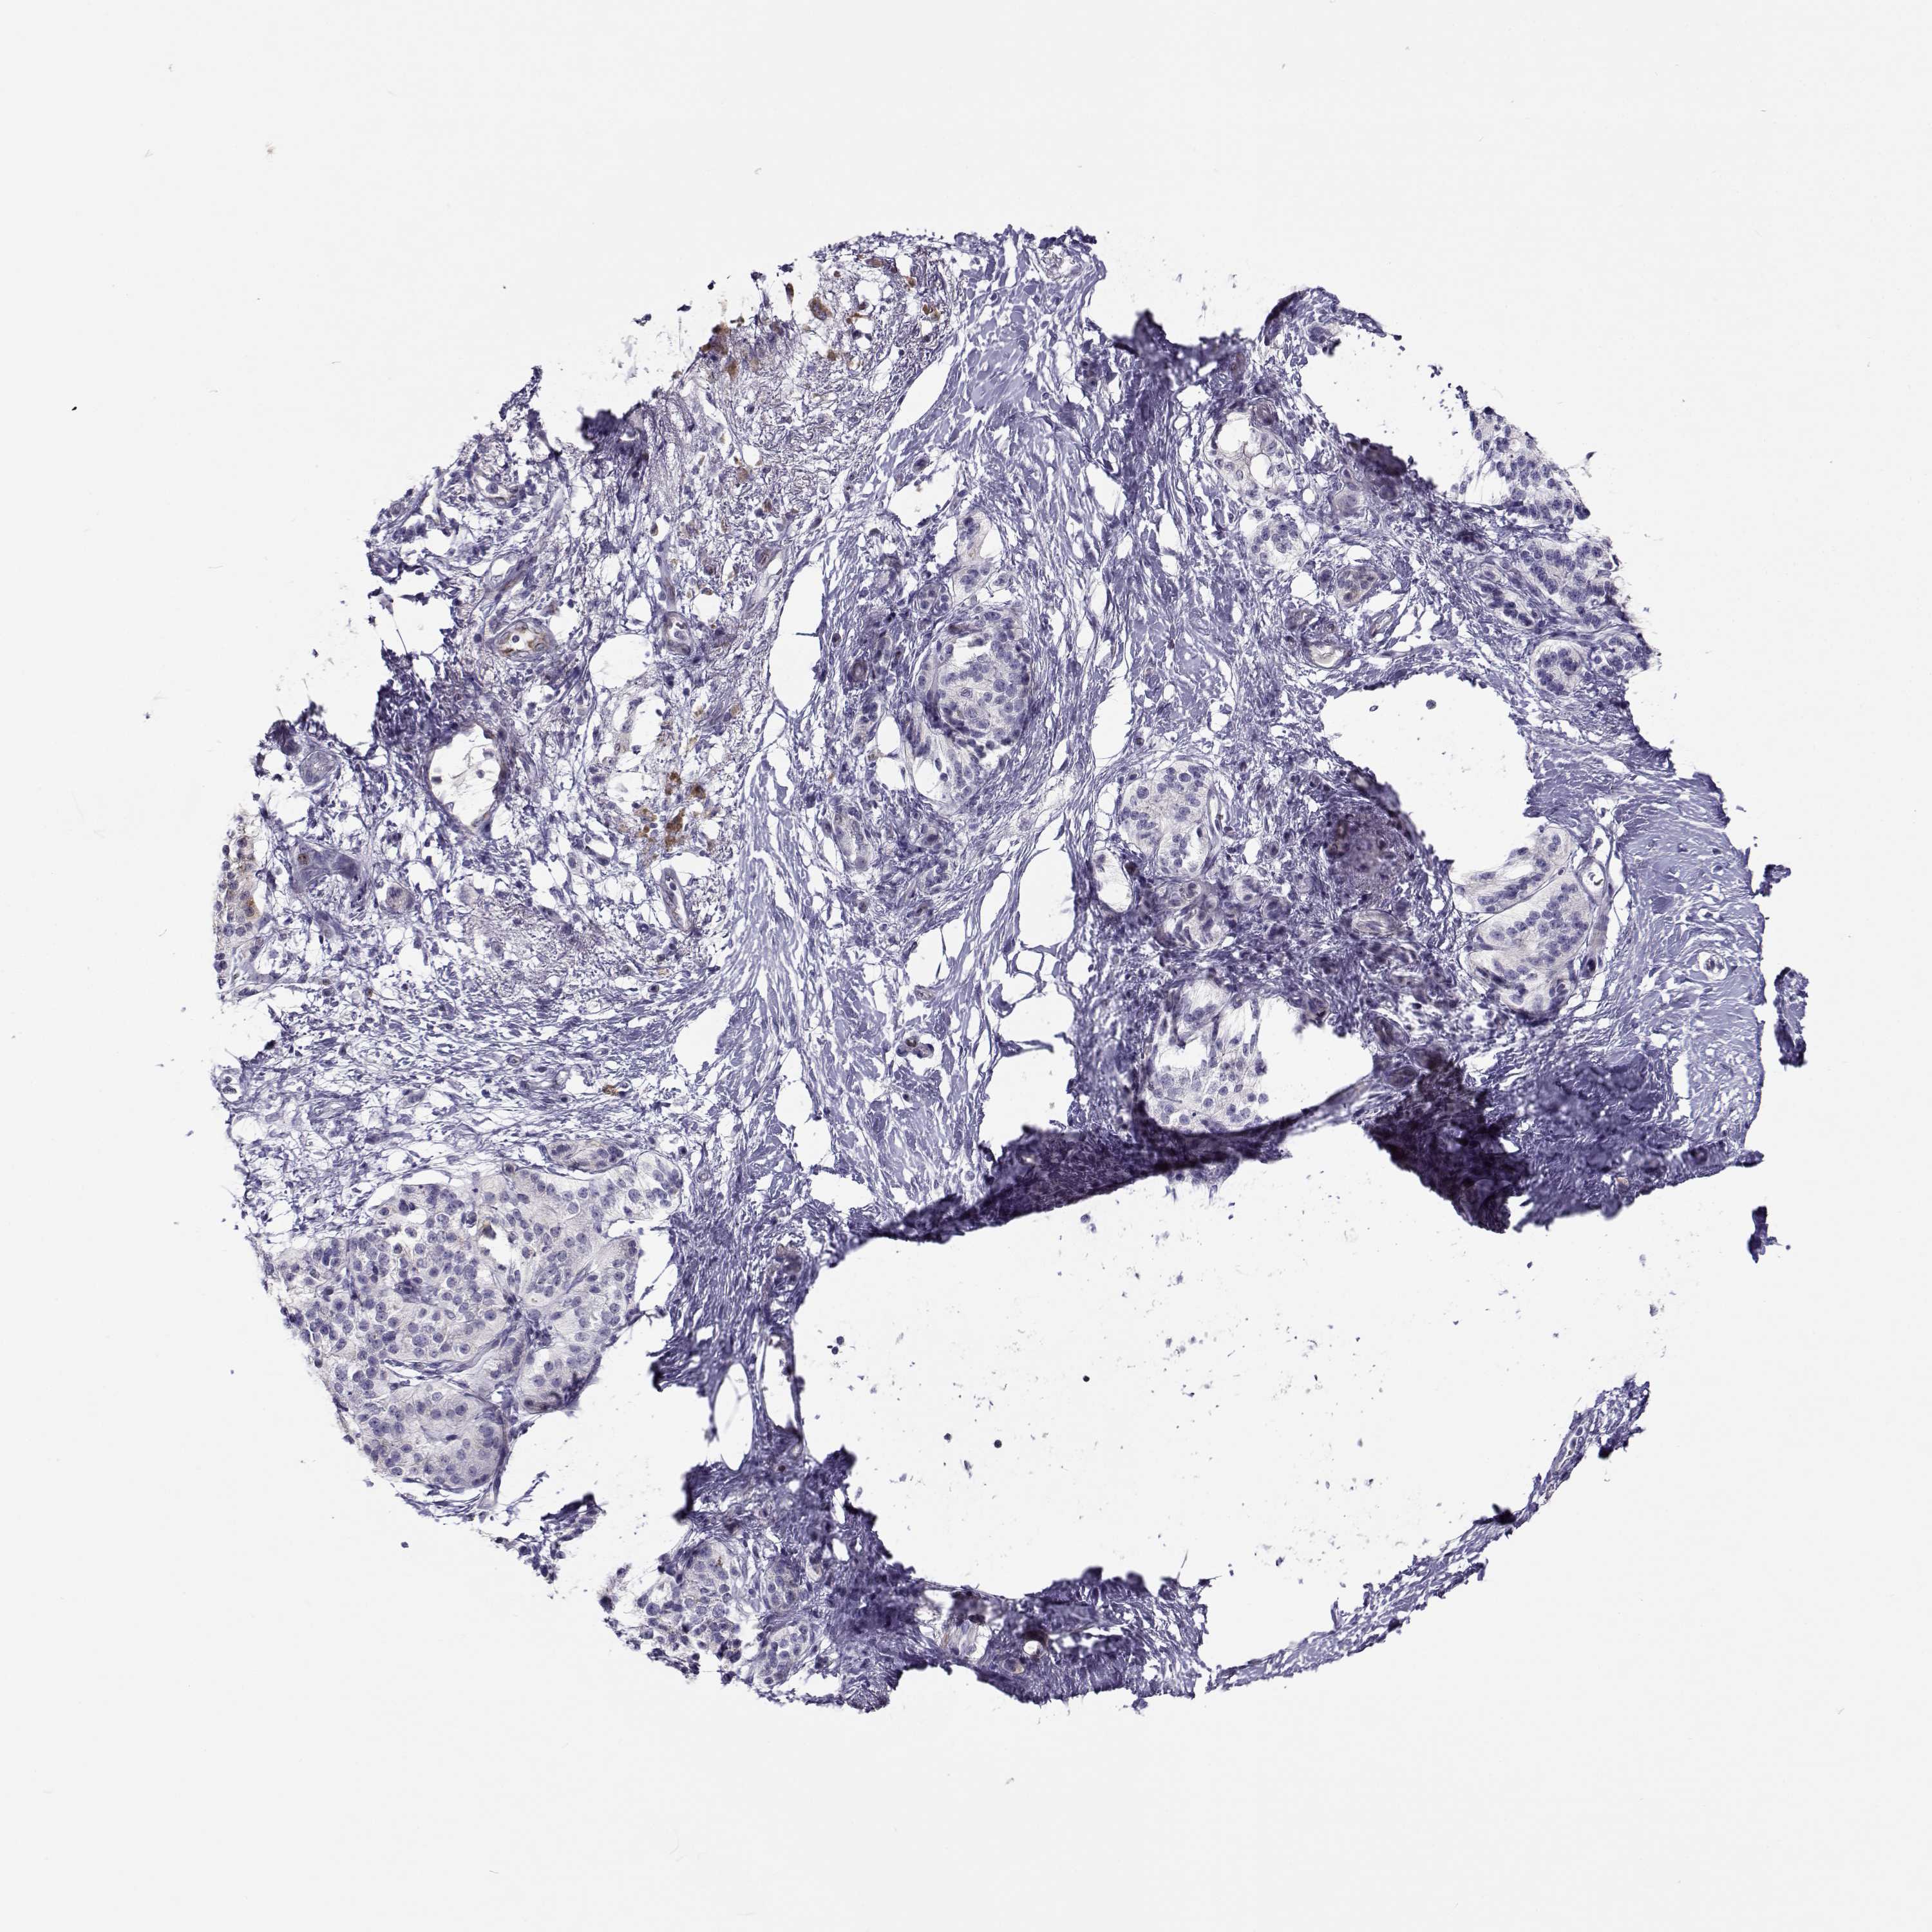

PANCREATIC CANCER - Protein expressioni

A mouse-over function shows sample information and annotation data. Click on an image to view it in a full screen mode. Samples can be filtered based on level of antibody staining by selecting one or several of the following categories: high, medium, low and not detected. The assay and annotation is described here.

Note that samples used for immunohistochemistry by the Human Protein Atlas do not correspond to samples in the TCGA dataset.

Antibody stainingi

Antibody staining in the annotated cell types in the current human tissue is reported as not detected, low, medium, or high, based on conventional immunohistochemistry profiling in selected tissues. This score is based on the combination of the staining intensity and fraction of stained cells.

Each image is clickable and will lead to virtual microscopy that enables deeper exploration of all samples and also displays staining intensity scores, fraction scores and subcellular localization as well as patient and tissue information for each sample.

Antibody HPA064874

Staining

High

Medium

Low

Not detected

Intensity

Strong

Moderate

Weak

Negative

Quantity

>75%

75%-25%

<25%

None

Location

Nuclear

Cytoplasmic/membranous

Cytoplasmic/membranous,nuclear

Adenocarcinoma, NOS